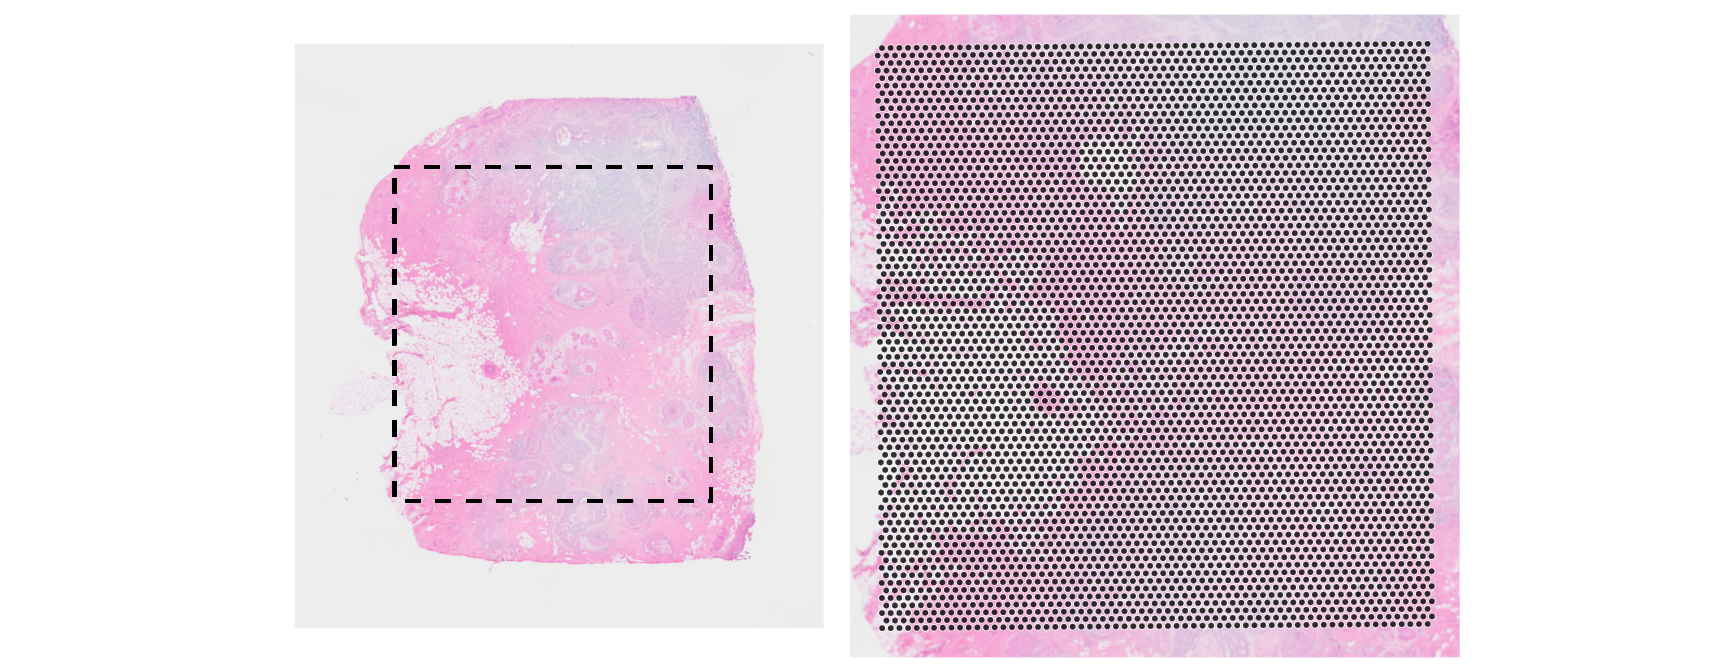

Code

xy <- spatialCoords(vis) * scaleFactors(vis)

ys <- nrow(imgRaster(vis)) - range(xy[, 2])

xs <- range(xy[, 1])

box <- geom_rect(

xmin=xs[1], xmax=xs[2], ymin=ys[1], ymax=ys[2],

col="black", fill=NA, linetype=2, linewidth=2/3)

plotVisium(vis, spots=FALSE, point_size=1) + box +

plotVisium(vis, point_size=1, zoom=TRUE) +

plot_layout(nrow=1) & facet_null()